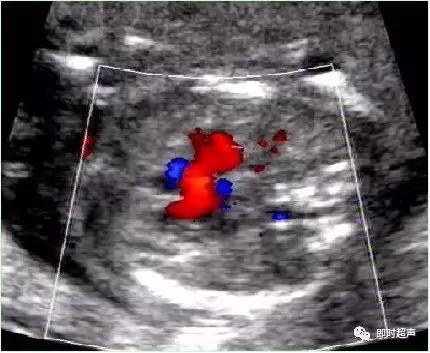

单脐动脉超声诊断

单脐动脉胎儿仅见一根脐动脉于膀胱一侧,经膀胱腹部横切面可判断左侧或右侧脐动脉缺如。羊水中脐带纵切面仅见两根血管并行或螺旋状排列, 横切时可见两个大小不一的圆环并行排列,彩色多普勒显示一红一蓝彩色血流信号。